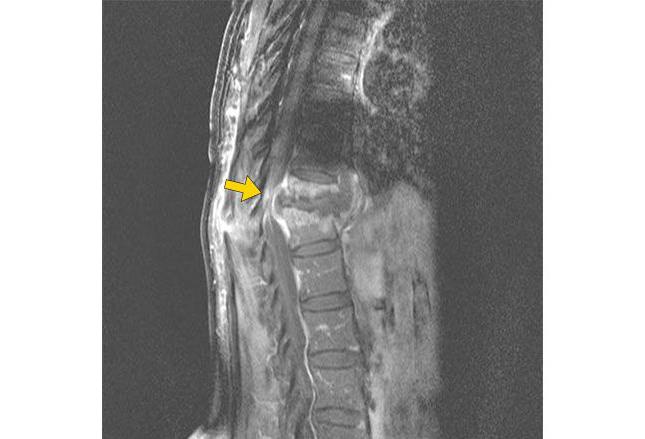

Согласно статистике, большая часть пациентов с этим диагнозом — люди пожилого возраста. Примерно в 60% случаев болезнь поражает позвоночник, что ведет к инвалидности. Гониты, спондилиты и кокситы — это самые распространенные нарушения, которыми сопровождается внелегочный туберкулез. Симптомы практически не проявляются на ранних стадиях заболевания.

Иногда пациенты отмечают болезненность в области пораженной части опорно-двигательного аппарата. Если недуг развивается по типу артрита, то можно отметить дискомфорт, припухлость в мелких суставах, ограниченность движений. Если речь идет о поражении позвоночника, то растущая гранулема нередко сдавливает нервные корешки, что сопровождается различными неврологическими расстройствами.

К сожалению, люди обращаются к врачу на поздних стадиях, когда уже присутствуют такие осложнения внелегочного туберкулеза, как абсцессы, стойкие деформации скелета, свищи. Диагностика заболевания может быть сопряжена с некоторыми трудностями, так как клиническая картина здесь весьма смазана. В большинстве случаев даже после грамотно проведенного лечения деформации костей остаются.

Наиболее частая локализация внелегочного туберкулеза — в тканях костей и суставов (более 20% всех случаев). У больного происходит поражение различных скелетных отделов (позвоночник, колени, тазобедренные суставы).

На следующей картинке вы видите части скелета, которые чаще всего поражает туберкулез:

При выходе туберкулёзного воспаления за пределы позвоночника наступает второй этап:

- Усиление симптомов предыдущей фазы.

- Появляются выраженные боли в одном из отделов позвоночника, что влечет за собой понижение активности больного.

- Ухудшается осанка, меняется походка.

- Снижается интенсивность боли и она полностью прекращается в состоянии покоя.

- Мышцы стабилизаторы позвоночника находятся в постоянном напряжении.

Третий этап туберкулеза позвоночника характеризуется переходом воспалительного процесса на ткани других позвонков: